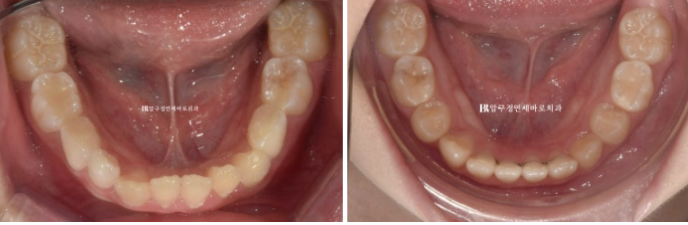

지난 치료를 요약해보면 초진 시 앞니 4개씩 나온 상황입니다.

유치가 10개나 남은 상황이나 아이들이 이 빠지고 나는 속도는 사람마다 달라 정확한 예측은 어렵습니다.

2022.09

아역배우 친구여서 보이는 철사교정 말고 인비절라인 퍼스트 어린이 투명교정 장치로 시작했습니다.

장치를 열심히 착용했고 2022년 9월부터 2023년 5월까지 변화 모습입니다.

2022.09~2023.05